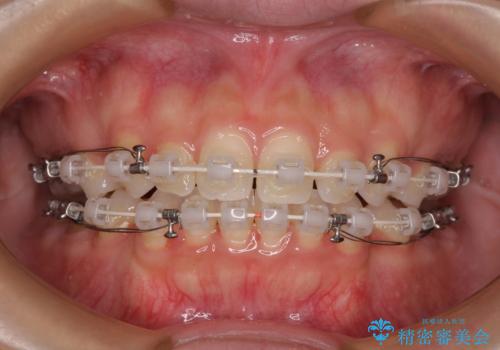

前歯のデコボコとクロスバイト ワイヤー装置での抜歯矯正

- 前歯のデコボコとクロスバイトを気にして来院された患者様です。

上下ともにデコボコはそれほど強くありませんでしたが、非抜歯では口元が突出した仕上がりとなる可能性があるため、上下左右の第一小臼歯4本を抜歯し、ワイヤー装置での抜歯矯正を行うこととしました

スペースを閉じるために期間を要しましたが、無事に綺麗な口元に仕上げることができました。